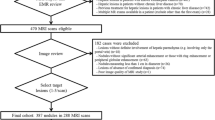

We searched the electronic database of our institution and identified 742 consecutive patients who underwent 1130 abdominal MR examinations obtained between January 2010 and June 2013. Among them, we retrospectively identified 102 patients (101 men & 1 woman; mean age, 63 years; range 49–81 years) with MR exams suggesting a newly developed HCC. Since our hospital is a military institution, our patients are skewed toward male gender. Of our initial patients, we excluded ten patients for the following reasons which may preclude the quantitative and visual assessment of signal intensity of the hepatic parenchyma or HCC: (1) infiltrative HCC (n = 3); (2) bile duct obstruction (n = 1); (3) more than 10 HCCs (n = 3); and (4) hyperintense HCCs on hepatobiliary phase images (n = 3). Of the remaining 92 patients, we further excluded three patients who did not have available relevant laboratory tests for the determination of liver disease severity within three months before or after liver MR examinations. In addition, we excluded three patients in whom HCCs were not confirmed by pathology or were not consistent with our reference standard (described below in detail). Thus, our study population consisted of 86 patients (86 men; mean age, 63 years; range 49–81 years) with HCCs.